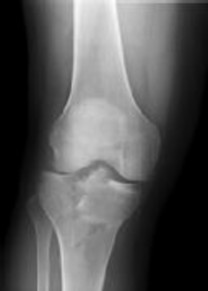

Figures 1 and 2 are the radiographs of a 35-year-old man who is brought into the emergency department after a motor vehicle collision. He is complaining of isolated knee pain. Examination reveals swelling, blood filled blisters, popliteal ecchymosis, joint line pain, and limited knee joint motion. His pulses and sensation are normal.

This knee injury is best described as a